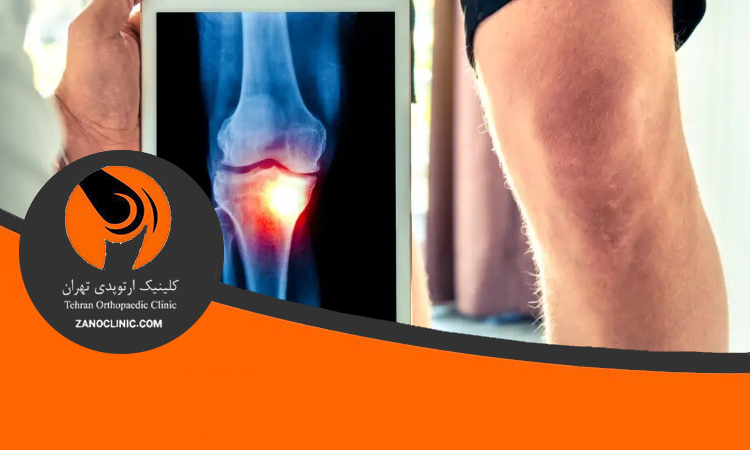

مفصل زانو از نوع مفصل لولایی است که بین استخوان ران (فمور) و استخوان ساق پا (تیبیا) قرار دارد و استخوان کوچک کشکک (پاتلا) نیز در جلوی آن نقش محافظ و افزایش دهنده ی کارایی حرکات را دارد. این مفصل از نظر عملکردی مسئول انتقال وزن بدن از قسمت بالایی به پایین تر و در عین حال تأمین ثبات هنگام ایستادن و حرکت است.

آناتومی مفصل زانو به گونه ای طراحی شده که بتواند نیروهای فشاری و کششی بالایی را تحمل کند. در هنگام راه رفتن، زانو باید وزن بدن را تا چند برابر در هر گام کنترل نماید. به همین دلیل، ساختارهای مختلف آن شامل استخوان ها، رباط ها، غضروف ها و عضلات، با دقتی شگفت انگیز هماهنگ عمل می کنند.

عملکرد زانو به ویژه در ورزش هایی مانند فوتبال، دویدن یا کوهنوردی اهمیت زیادی دارد، زیرا این حرکات ترکیبی از فشار، خم شدن و چرخش را به مفصل وارد می کنند. کوچک ترین ضعف در یک جزء از اجزای زانو می تواند باعث درد، ناپایداری یا حتی آسیب جدی شود.